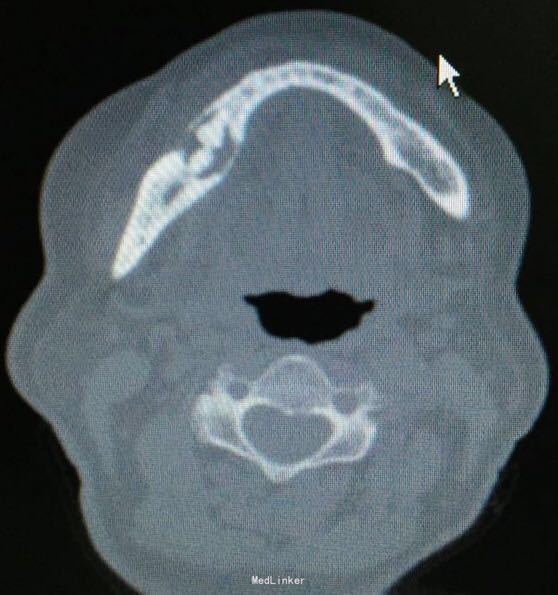

右下颌骨肿物待查

右下颌后牙拔牙后一年,偶有疼痛不适。拍片发现拔牙区有低密度影,于是来我科就诊,否认全身疾病.

46缺失,拔牙创愈合可。CT示46区低密度影,中间密度增高影。

右下颌肿物待查。全麻下切开刮治,可见死骨。送病理。

创口愈合可。等待病理结果,可能是什么?骨纤?